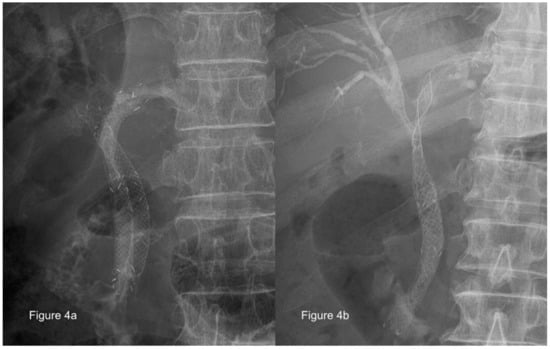

4.1. Bilateral or Unilateral Drainage

- Vienne, A.; Hobeika, E.; Gouya, H.; Lapidus, N.; Fritsch, J.; Choury, A.D.; Chryssostalis, A.; Gaudric, M.; Pelletier, G.; Buffet, C.; et al. Prediction of drainage effectiveness during endoscopic stenting of malignant hilar strictures: The role of liver volume assessment. Gastrointest. Endosc. 2010, 72, 728–735. [Google Scholar] [CrossRef]

- Inal, M.; Akgul, E.; Aksungur, E.; Seydaoglu, G. Percutaneous placement of biliary metallic stents in patients with malignant hilar obstruction: Unilobar versus bilobar drainage. J. Vasc. Interv. Radiol. 2003, 14, 1409–1416. [Google Scholar] [CrossRef] [PubMed]

- Lee, S.H.; Park, J.K.; Yoon, W.J.; Lee, J.K.; Ryu, J.K.; Yoon, Y.B.; Kim, Y.T. Optimal biliary drainage for inoperable Klatskin’s tumor based on Bismuth type. World J. Gastroenterol. 2007, 13, 3948–3955. [Google Scholar] [CrossRef] [PubMed]

- Rerknimitr, R.; Kladcharoen, N.; Mahachai, V.; Kullavanijaya, P. Result of endoscopic biliary drainage in hilar cholangiocarcinoma. J. Clin. Gastroenterol. 2004, 38, 518–523. [Google Scholar] [CrossRef] [PubMed]

- Paik, W.H.; Park, Y.S.; Hwang, J.H.; Lee, S.H.; Yoon, C.J.; Kang, S.G.; Lee, J.K.; Ryu, J.K.; Kim, Y.T.; Yoon, Y.B. Palliative treatment with self-expandable metallic stents in patients with advanced type III or IV hilar cholangiocarcinoma: A percutaneous versus endoscopic approach. Gastrointest. Endosc. 2009, 69, 55–62. [Google Scholar] [CrossRef] [PubMed]